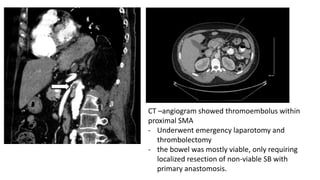

CT –angiogram showed thromoembolus within

proximal SMA

- Underwent emergency laparotomy and

thrombolectomy

- the bowel was mostly viable, only requiring

localized resection of non-viable SB with

primary anastomosis.